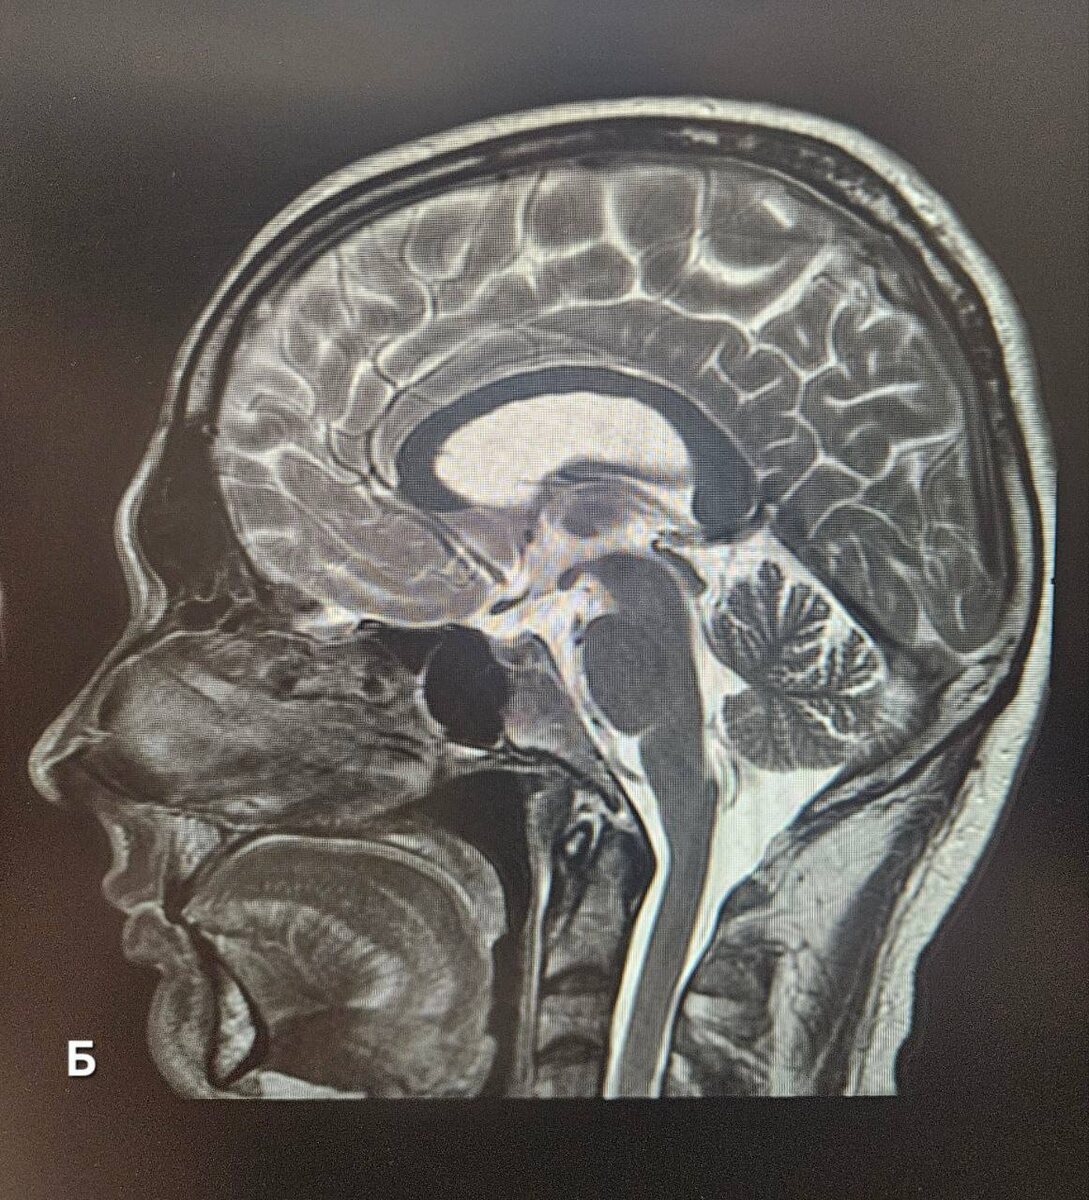

МРТ мужчины 😠 и женщины 💅